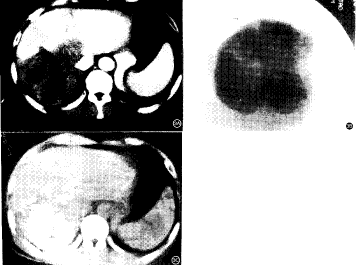

图1 患者 男,60岁。乙型肝炎病史11年。超声检查发现肝右叶占位病变,并经针吸活检证实为肝细胞癌。A.肝脏CT增强扫描见肝右叶一明显强化病灶,大小约2.0cm×2.5cm。其外侧见一3.0cm×3.5cm大小的囊性病变,影像学诊断为肝囊肿。B.经用超液化碘油行TAE治疗16天后CT平扫复查,见肝癌病灶内碘油积聚密实,但肝右叶正常肝实质内也见大量碘油沉积。C.同一检查见肝右叶后段非病变区也有大量碘油沉积 图2 患者 男,38岁。患乙型肝炎及肝硬化7年。影像学检查及活检证实为肝右叶小肝癌。A.应用超液化碘油栓塞后17天CT复查,见碘油积聚于病灶内,同时病灶周围组织内也见大量碘油积聚。B.肝右叶非病变区内亦见大量碘油积聚